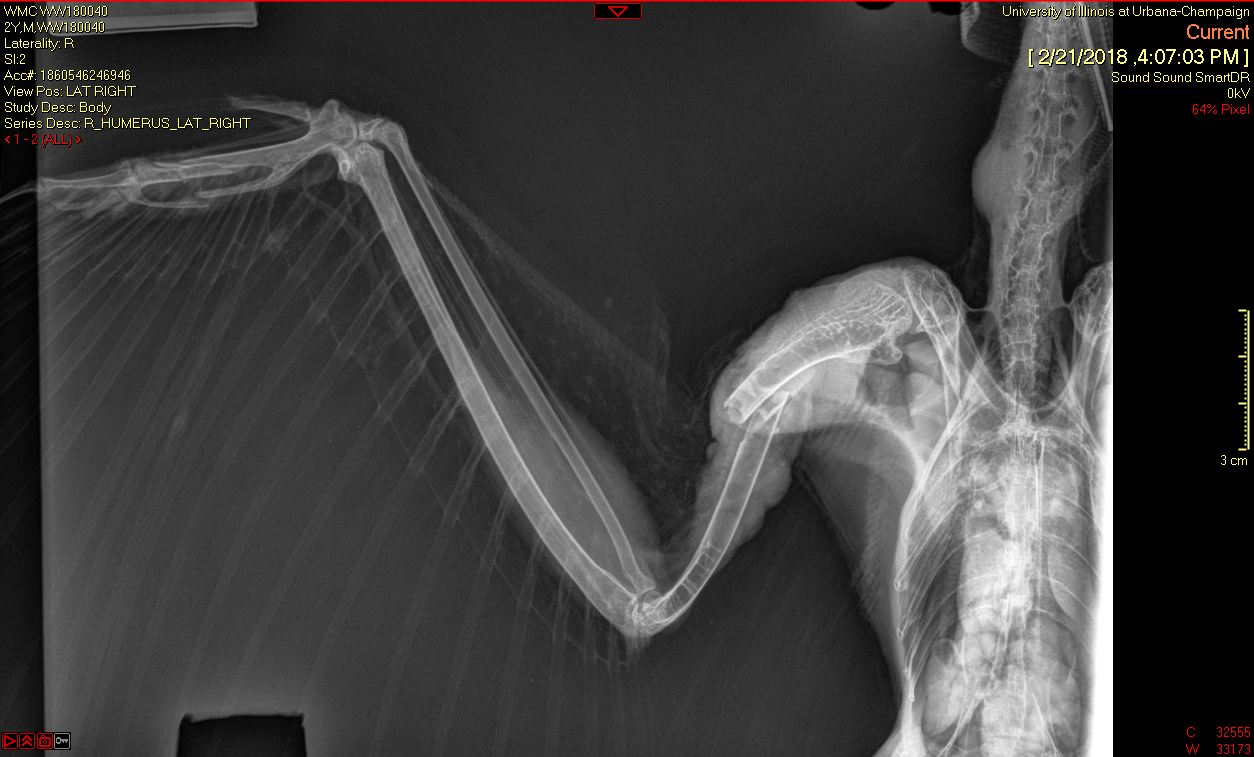

A Barred Owl was transferred to the Wildlife Medical Clinic from a nearby veterinary clinic on February 20th after being hit by a car on February 18th. In their initial exam, the team noticed an open fracture on the middle of the right humerus of the wing. Radiographs (x-rays) showed that the wing had been rotated a complete 360 degrees!

Once the wing was rotated back into normal position, the team had to wait to assess whether the portion distal to the rotation (closer to the wing tip) still had healthy blood supply. Once this was ensured, they determined the owl was a good candidate for surgery to repair the humeral fracture.

The team was happy with the placement of the pins! However, as they continued to monitor the owl, they noticed it squinting its right eye. On further investigation, team leaders determined that the owl could not see out of its right eye and that an injury was causing discomfort. So, the owl underwent surgery again, this time an evisceration procedure to remove the eye.